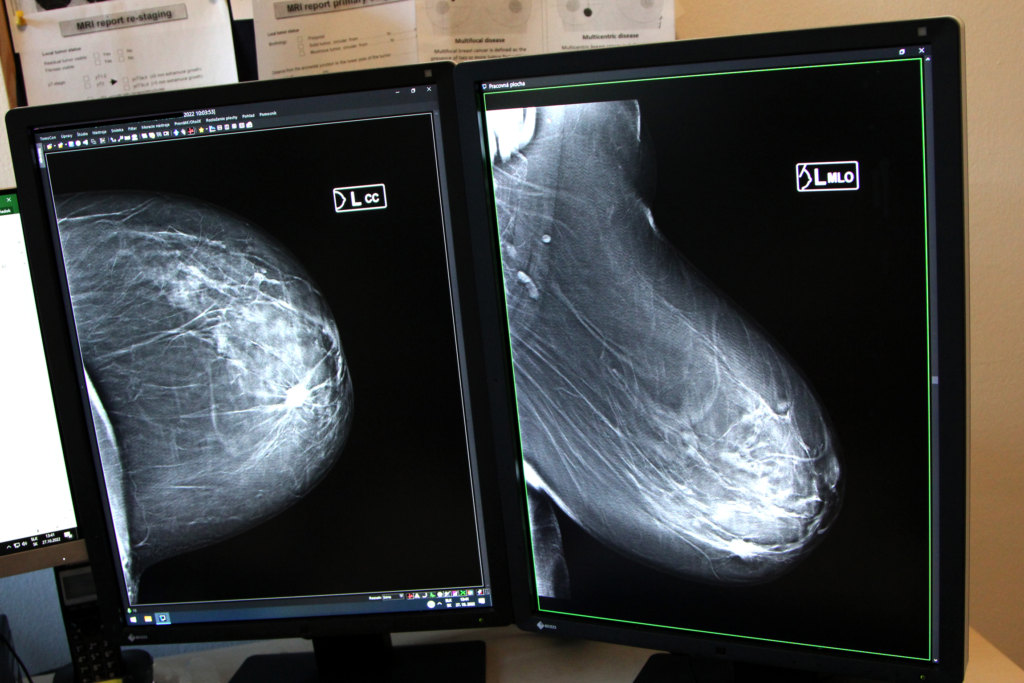

Nie. Keby to bolo také jednoduché, nemusíme používať zobrazovacie vyšetrenia ako mamografia, ultrazvuk a magnetická rezonancia. Keď sa rakovina prejaví hrčkou, ide obvykle o pokročilejší nález. To však neznamená, že samovyšetrovanie je úplne zbytočné, lebo žena spozná svoje prsníky a vie lepšie posúdiť zmeny. Treba vziať do úvahy aj menštruačný cyklus, lebo počas neho sa menia hormonálne hladiny, a to sa spája so zdurením prsníkovej žľazy. Často si môžeme nahmatať zdurenia alebo hrčky v prsnej žľaze medzi ovulačnou a menštruačnou fázou. Až keď sa hrčka po menzese nestratí, je dôvod kontaktovať svojho gynekológa alebo praktického lekára.

Ani nie tak veľkosť, ako hustota, čiže denzita prsníkov. Čím je vyššia hustota žľazy, tým je väčšie riziko vzniku karcinómu prsníka.

V úvode skríningu pozývali ženy na mamografie poisťovne, ktoré neboli na mamografii za posledné dva roky a boli vo vekovom limite 50 až 69 rokov. Na takéto pozvanie bola veľmi nízka účasť na mamografických vyšetreniach. Mnohé ženy prišli na takzvanú preventívnu mamografiu, ktorá má taký istý zmysel, ale nevykonáva sa na preverenom pracovisku akreditovanom ako skríningové pracovisko. Dokopy chodí na pravidelné mamografické vyšetrenia približne tridsať percent žien, čo je veľmi nízke v porovnaní s krajinami, kde je skríningový program dlho etablovaný a kde majú robustné dáta, že to vedie k poklesu mortality.

Aspoň sedemdesiat percent. Vtedy by sa dosiahol pokles úmrtnosti o tridsať až štyridsať percent. Ročne u nás umrie na rakovinu prsníka okolo deväťsto žien, čiže tristo z nich by sme vedeli zachrániť, keby sa pravidelne zúčastňovali na skríningovej mamografii.

Myslia si, že mamografia je škodlivá, chceme im ňou ublížiť a že máme aj lepšie diagnostické metódy ako ultrazvuk alebo termovízia. Podotýkam, že žiadna z týchto metód nie je uznaná ako skríningová metóda a nemá taký záchyt karcinómu prsníka, aby sme ju mohli odporúčať ako skríningovú metódu.